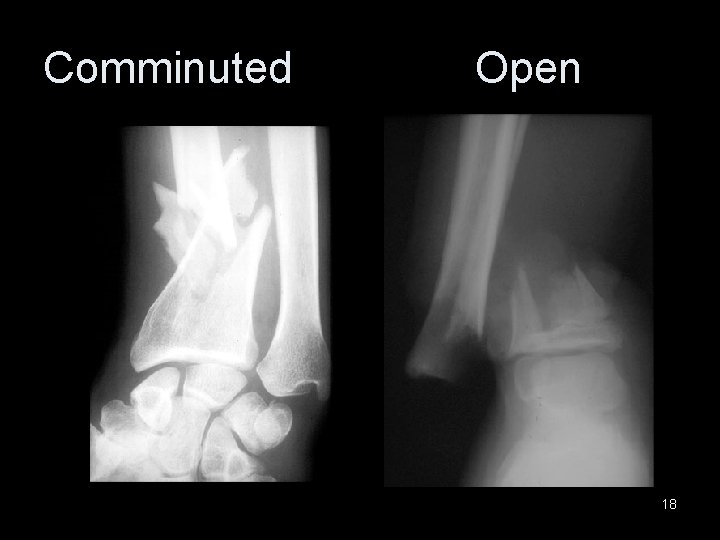

Comminuted Open 18